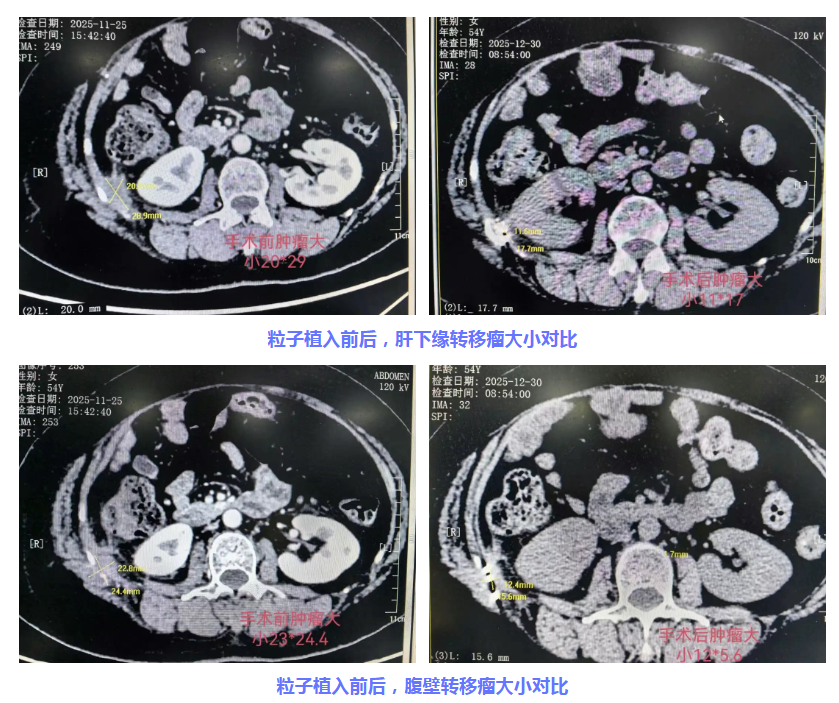

2025年11月28日,在CT精准引导下,经管医师张剑飞及团队成功为程女士肝下缘及腹壁转移瘤植入了30颗碘125粒子。手术历时1小时,过程顺利,创伤微小。在此过程中,核医学科、放射科等科室高效协同,提供了粒子源准备、术前精准剂量规划与术后验证等关键技术支持,确保了治疗的安全与精准。

术后仅半个月,程女士的腹壁疼痛感得到显著缓解,生活质量大幅提升。随着疼痛的有效控制,患者成功停用了此前不得不依赖的口服止痛药,困扰已久的便秘问题也随之迎刃而解。